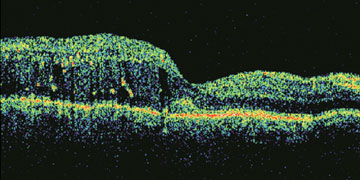

In addition to the clinical examination, colour fundus photography, fluorescent angiography and optical coherence tomography (OCT) scan contribute in the evaluation and management of diabetic retinopathy. High quality OCT machines are now available in our city. This generates cross sectional scan of retina with great details.